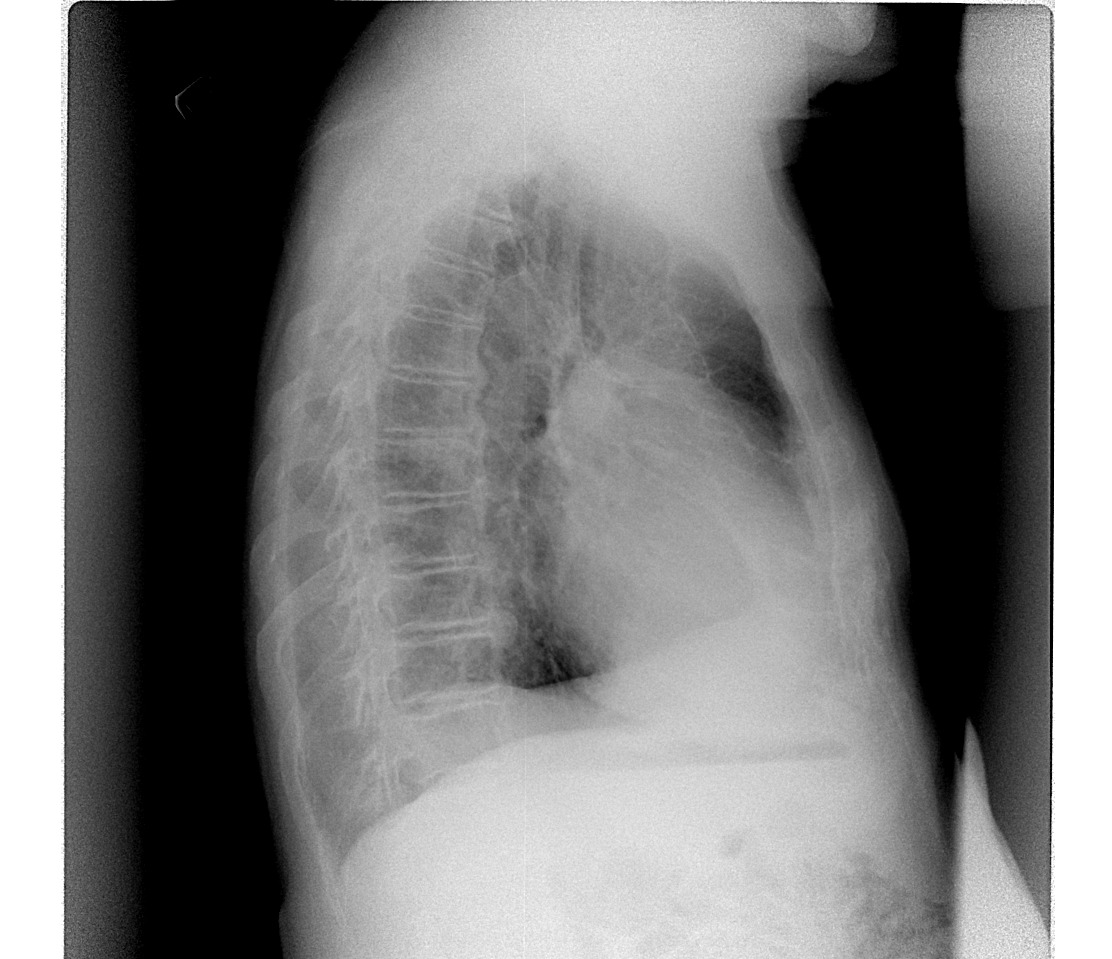

Шварта. Видно на боковом.

Эти так называемые дела можно назвать уплотнённой междолевой плеврой.)) Это главная которая. У кардиологических, бывает, плотнеет она.